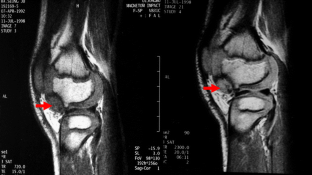

We found that, unlike in osteochondroma, DEH was radiographically not clearly separable from the underlying or host bone with preserved cortical bone and marrow continuity. The finding in the talus distinguished DEH from (osteochondroma-like) parosteal osteosarcoma, in which a radiolucent demarcation line clearly separated the tumor from the host bone. The DEH mass had a well-defined low to intermediate signal intensity on T1-weighted images and an intermediate to high signal intensity on T2-weighted images, with irregularity of the articular surface. Simple excision was performed in all patients. The excision was complete in six patients and incomplete in two patients whose lesions was juxta-articular in the ankle and articular in the knee, respectively. The residual mass slowly absorbed and vanished, resulting in mild flaring of the affected portion of the epiphysis. No local recurrence or complication was seen in any of the eight patients.

Although the radiographic signs of DEH are characteristic, (osteochondroma-like) parosteal osteosarcoma should be differentiated from DEH when there is a radiolucent separation line between the mass and host bone in the talus. Simple excision was effective in the management of DEH if the deformity was not complicated. Incompletely excised masses resolved and vanished with time.